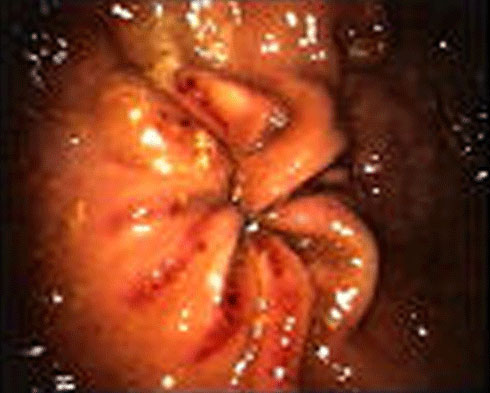

- 2 = Leichte Ulzeration: Multifokale oder generalisierte Ulzerationsbereiche, die oberflächlich erschienen mit/ ohne Hyperämie und leichter/ mittlerer Hyperkeratose.

- 3 = Mittlere Ulzeration: extensive oberflächlich wirkende Läsionen oder tiefere fokale Läsionen mit/ohne Proliferation entlang der Läsionsränder und kleine Blutungen.

- 4= Schwere Ulzeration: tief wirkende multifokale oder generalisierte Ulzeration mit oder ohne mittlere Schleimhaut-Wucherung entlang der Läsionsränder und aktiver Blutung.

- 5 = Extensive schwere Ulzeration: ausgedehnte Bereiche tiefer Ulzerationen mit/ohne ausgedehnte Schleimhaut-Wucherungen entlang der Läsionsränder und aktiver Blutung.

| Magenulkus-Index | 3 | 3 | 4 | 3 | 2 | 4 |

| Kommentar | Lokale Läsionen und Blutung | Schwere lokale Läsionen um den Colon | Leichte Koliksymptome | Blutung | Leichte bis mittlere Entzündung, lokalisiert | grobflächig schwere Läsionen |

| Magenulkus-Index | 0 | 1 | 1 | 0 | 3 | 1 |

| Kommentar | keine Koliksymptome mehr | keine Koliksymptome mehr | Noch kleine Läsion mit Hyperkeratose | symptomfrei dem Besitzer zufolge | Keine Veränderung in den Symptomen | Bessere Leistung und ruhigeres Verhalten |